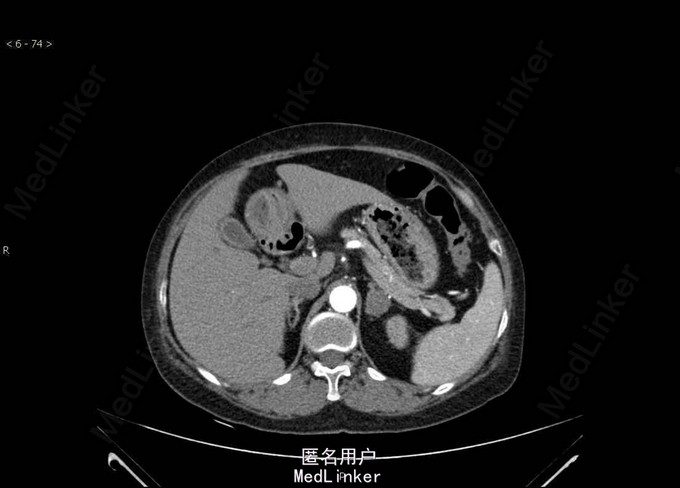

Bp:168/112mmHg,其余无特殊。 肾上腺CT:左侧肾上腺结节,考虑腺瘤可能性大。双肾、脾脏多发囊肿。双肾动脉CTA检查未见明确病变。左侧肾上腺见一大小约25mm×22mm的结节影,CT值约40HU,增强扫描可见强化。右侧肾上腺大小、形态及密度未见明确异常。 术后病理示肾上腺皮质腺瘤。